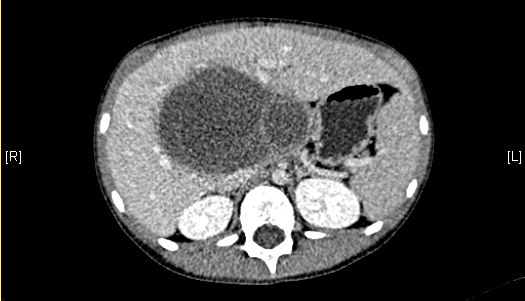

术前CT检查:

静脉期

一般情况:CH-001-LT-000009,男,7岁,身高128cm,体重24.5kg。

现病史:因感冒后出现上腹部不适,至当地医院就诊,查腹部超声示“肝脏占位”,遂至青岛妇女儿童医院就诊,查腹部CT示“肝脏占位”,未予特殊治疗,为求进一步诊治来我院就诊,门诊以"肝脏占位"收入院。

腹部超声示:肝内包块。腹部CT:肝脏占位,血管瘤?上腹部增强CT:肝左内叶-右前叶交界区、尾叶囊实性团块影,考虑肿瘤(胆管囊腺瘤?间叶性错构瘤?)